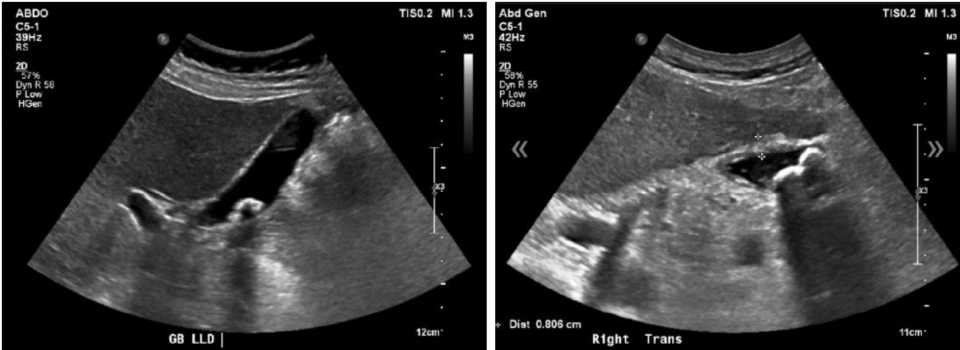

Gallbladders Gone Wild

This PoCUS-focused post goes beyond simple image interpretation and helps clinicians think systematically at the bedside. It teaches optimization techniques, pattern recognition, and common pitfalls, with the goal of improving accuracy and reducing unnecessary imaging.

Key teaching points:

-

Optimizing probe selection, depth, and gain

Consistently visualizing the gallbladder neck and cystic duct

Distinguishing true stones from artifacts

Recognizing secondary signs of acute cholecystitis

Knowing when bedside ultrasound is enough, and when it isn’t